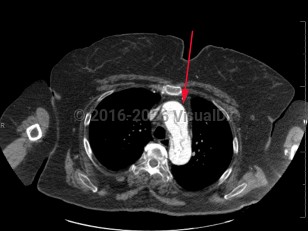

- CT angiogram of chest / abdomen / pelvis.

Aortic dissection is an intramural tear of the aorta. Aortic dissection is a life-threatening emergency. Tears often occur in the intimal layer of the aorta, with blood collecting in the medial layer. Back pain is the common presenting symptom, but it may also present with chest pain, dyspnea, or a new neurologic deficit. Syncope and hypotension occur less frequently. Aortic dissections most often occur in older men.

- Type A – dissection involving ascending aorta

- Type B – dissection that does not involve ascending aorta (ie, aortic arch and descending aorta)